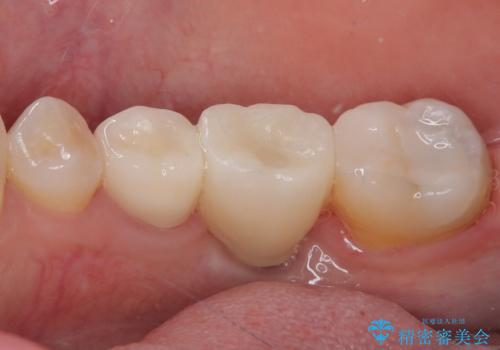

- インレーブリッジをインプラントにやり替えて銀歯を白くしたいとのことで来院された患者様です。

既に抜歯をして歯のない箇所にはインプラント治療をし、ブリッジの土台となっている歯のうち、手前側の小臼歯は既に根管治療をされている歯なのでオールセラミッククラウンへのやり替え、奥側の大臼歯はセラミックインレーへのやり替えをしていくこととしました。

根管治療のやり直しは希望されなかったため、土台の部分からのやり替えです。